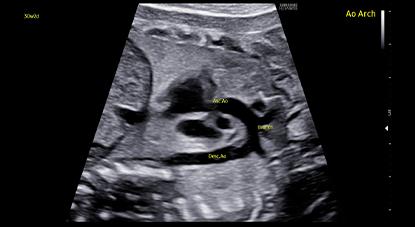

Meet the new premium women’s ultrasound designed to elevate confidence and efficiency in women’s healthcare.The new HERA W9 ultrasound system combines superior imaging technology with ergonomic design to advance workflow.Featuring the innovative Crystal Architecture™ and premier image processing technologies,HERA W9 produces realistic, high-resolution images for exceptional accuracy.

Crystal Architecture™, an imaging architecture that combines CrystalBeam™ and CrystalPure™, while based upon S-Vue Transducer™, is to provide crystal clear image.

CrystalBeam™ utilizes Arbitrary Waveform Transmission, Massive Parallel Beamforming,

and Synthetic Aperture technologies to produce a faster frame rate and improved image uniformity.

CrystalPure™ imaging engine help you to make more confident diagnoses with fundamental 2D images and enhanced color performance. It also lessens the incidence of clutter and boosts the level of color signal processing.

ShadowHDR™ selectively applies high-frequency and low-frequency of the ultrasound to identify shadow areas where attenuation occurs

ClearVision provides clearer tissue boundaries using the noise reduction filter and generates sharp 2D images. It reduces halo artifact that occurs when the tissue contour is enhanced, and removes noises on the tissue boundaries.

HQ-Vision™ provides clearer images by mitigating the characteristics of ultrasound images that are slightly blurred than the actual vision.